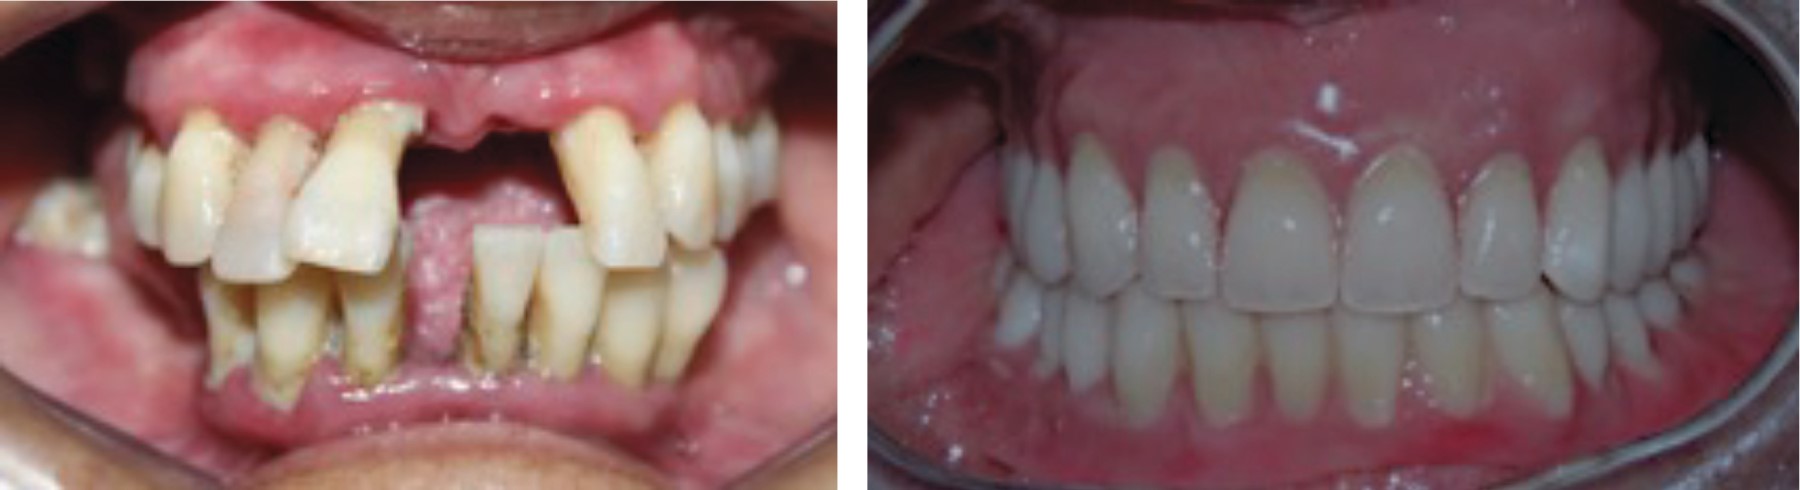

A la exploración clínica intrabucal presenta cálculo dental supra- y subgingival, movilidad dental generalizada y frenillo bucal superior con inserción baja (Figura 2).

Figura 2